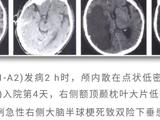

患儿女,41日龄,因“易激惹6d”于2017年4月天津市儿童医院神经内科住院。患儿易激惹、阵发哭闹,精神萎靡,睡眠不安,吃奶差,进行性加重,无抽搐,不伴发热、咳喘、吐泻。当地医院行头颅CT提示“双侧额、颞、顶、枕皮层下区、双侧桥脑、基底节区、丘脑多发性对称性低密度灶”(图1)。患儿为母亲第2胎第2产,胎龄39“周剖宫产出生,否认窒息史,出生体重3.0kg。父母健康,非近亲结婚;胞姐4岁,发育正常。